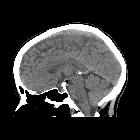

MRI

Central fat signal that attenuates on fat-saturated sequences is surrounded by calcification which results in low signal on most sequences and blooming on T2*/SWI sequences .

No enhancing component is helpful in distinguishing osteolipomas from tumors such as teratomas or craniopharyngiomas.